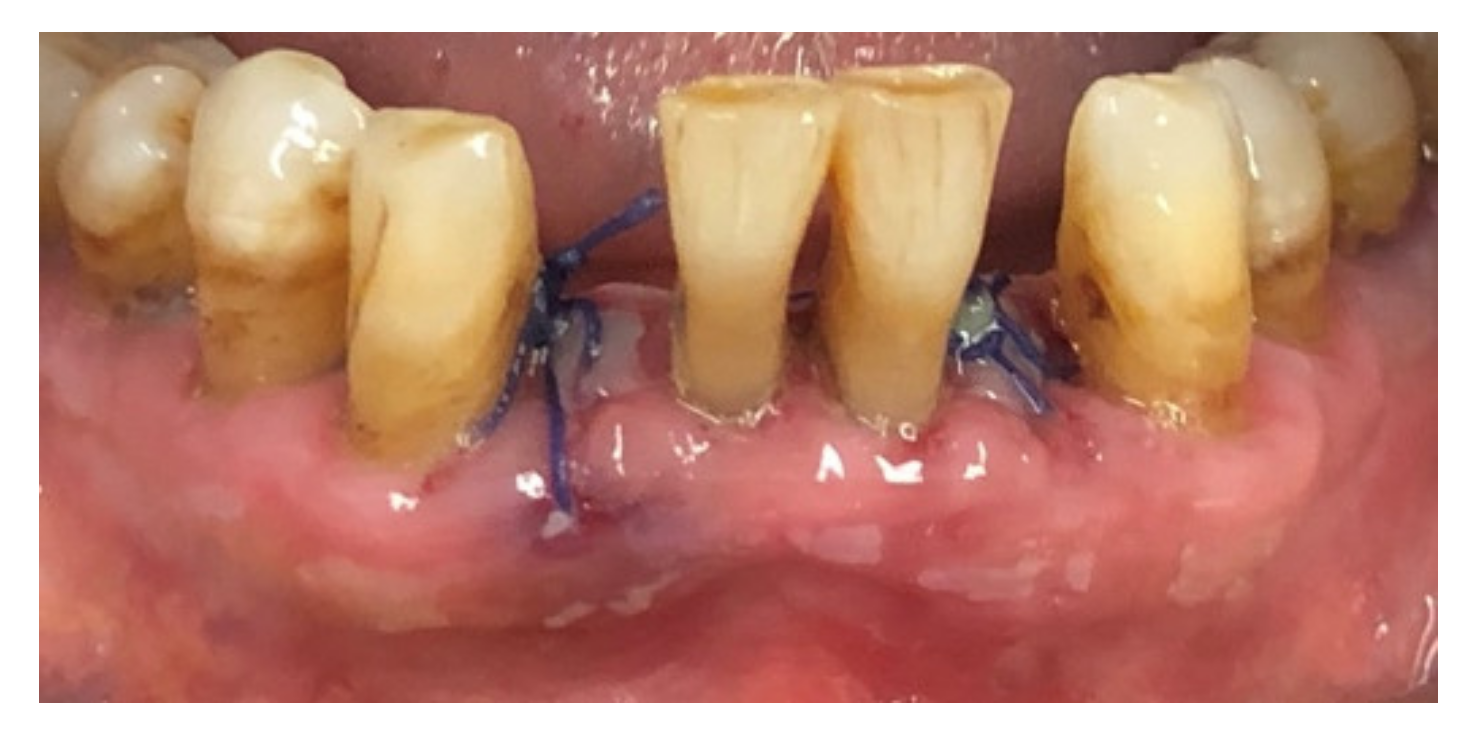

| Tissue colour: | 50% of gingiva red |

| Granulation tissue: | Present | |

| Incision margin: | Not epithelialized, with loss of epithelium beyond incision margin | |

| Suppuration: | Present | |

| Incision margin: | Not epithelialized, with connective tissue exposed | |

| Suppuration: | None | |

| Granulation tissue: | None | |

| Incision margin: | No connective tissue exposed | |

| Tissue colour: | 25% of gingiva red |

| Tissue colour: | All tissues pink |

| Suppuration: | None |

| 3 days | 2.15 ± 0.67 | 2; 0 | 1.75 ± 0.44 | 2; 0.25 | 0.038 |

| 7 days | 3 ± 0.73 | 3; 0.5 | 2.3 ± 0.47 | 2; 1 | 0.002 |

| 14 days | 4.2 ± 0.52 | 4; 0.25 | 3.8 ± 0.77 | 4; 1 | 0.074 |

| 28 days | 4.95 ± 0.22 | 5; 0 | 4.75 ± 0.44 | 5; 0.25 | 0.080 |

| Significance | 0.0001 | 0.0001 | |||